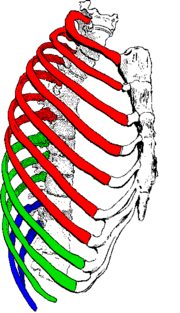

Ribs are described based on their location and connection with the sternum. Ribs that articulate directly with the sternum are called true ribs, whereas those that connect indirectly via cartilage are termed false ribs.

Attachment

The terms true and false rib describe rib pairs that are directly or indirectly attached to the sternum. The phrase true rib (Latin: costae verae), or fixed rib, refers to the first seven, or vertebrosternal, rib pairs. The phrase false rib (Latin: costae spuriae), or vertebrochondral ribs refers to the eighth-to-twelfth pairs of ribs. The eighth-to-tenth pairs of ribs connect to the sternum indirectly via the costal cartilages of the ribs above them.[1] Their elasticity allows ribcage movement for respiratory activity.

The phrase floating rib (Latin: costae fluitantes) refers to the two lowermost, the eleventh and twelfth, rib pairs; so-called because they are attached only to the vertebrae–and not to the sternum or cartilage of the sternum. These ribs are relatively small and delicate, and include a cartilaginous tip.[2]